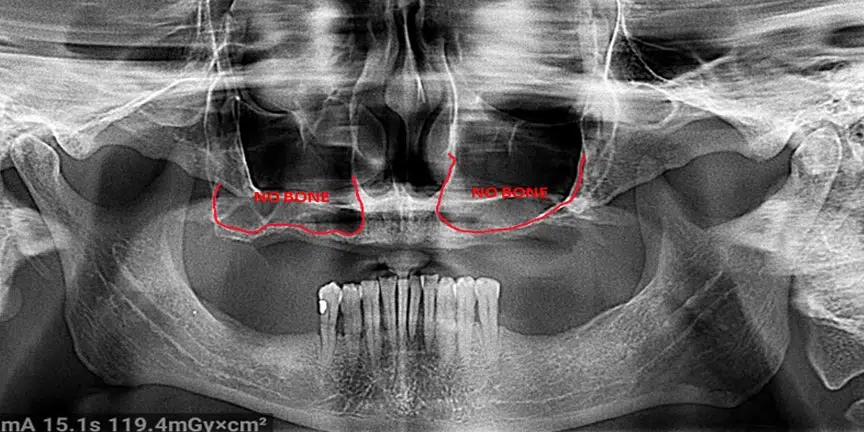

Severe Bone Loss